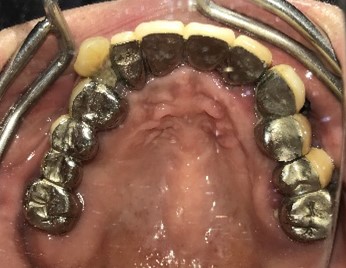

男性Iさん 50代(マグネット式入れ歯)

主訴

グラグラしている歯がある。歯並びをきれいにし、しっかり噛めるようになりたい。

治療内容

歯周病が進行し深刻な状態でした。保存することができない歯が上4本、下3本ありましたので、抜歯し、残った歯上4本、下7本の歯周病治療を徹底的にし、それらの歯を活用し上下マグネット式総入れ歯を入れました。

所感

治療前は、歯周病が進行し、重度に動揺している歯が4本あり、満足に食事ができない状況でした。マグネット式総入れ歯を装着後は、「なんでも思い通り噛むことができるだけでなく、歯並びもきれいになり、とても幸せです。」と、とても喜んでくださいました。

Before

赤丸は抜歯しました。上4本、下3本

After

【義歯を装着したところ】

【義歯を外したところ】

【マグネット式総入れ歯】

上顎

下顎